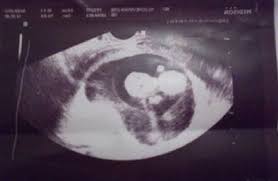

Your partner to ask any questions he may have, get to know your healthcare provider, hear the heartbeat, and see the baby via ultrasound. 10 week pregnant ultrasound can determine the exact site of pregnancy and if there is ectopic pregnancy it can be diagnosed. At 10 weeks pregnant, you're getting close to the end of your first trimester. 10 weeks 3 days pregnant. A month later hemmorage healed on it own and was back to normal activity.

Ultrasound at er confirmed pregnancy was fine. Either way, at ten weeks pregnant, you are about a quarter of the way through your pregnancy. Über 7 millionen englischsprachige bücher. Amniotic fluid also acts as a cushion to protect the developing baby from. There are some exciting developmental changes for your baby this.

You may be wondering when those pesky early pregnancy symptoms will start to fade or getting ready to share your big news with the world. This device is kind of like a microphone placed on the belly. Pregnancy symptoms & belly pictures. But if you are feeling some uncomfortable symptoms, things may seem like they're dragging. Ultrasounds are usually done in the first trimester to confirm a viable pregnancy, confirm the heartbeat, and confirm molar or ectopic pregnancies and also to assess abnormal gestation. A month later hemmorage healed on it own and was back to normal activity. 10 weeks 3 days pregnant. Ultrasound image of identical twins at 10 weeks, these babies share the same sac. By conducting a scan, she will be able to identify whether or not your baby is developing normally. Avoid wearing tight and constricting clothes. Pregnancy week 10 learn what is happening with your baby's development in week 10. His toes and fingers have taken a distinct form and started developing fingernails as well. At 10 weeks of pregnancy, the foetus weighs about 4gm and measures around 3.1cm from crown to rump.